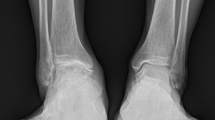

A detailed review of both pre- and postoperative functional outcomes and radiological variables was performed. The functional outcome was evaluated using the AOFAS hindfoot score. Pain was measured by the VAS score. Weightbearing anteroposterior (AP) and lateral views of the affected ankle joint were obtained for evaluation pre- and postoperatively (Fig. 3). The lateral talar station (LTS) was defined as the distance of the center of rotation of a circle fitting the talar dome to the tibial axis line on the weightbearing lateral view of the ankle joint14. The tibial lateral surface (TLS) angle was formed by the angle between the mechanical axis of the tibia and a line connecting the most anterior and posterior margin of the tibial plafond. The tibial anterior surface (TAS) angle was formed by the angle between the mechanical axis of the tibia and the tibial plafond on the AP view22. The talocrural angle was constructed by drawing a perpendicular line downward from the tibial plafond surface, which was crossed by a line drawn connecting the tips of the medial and lateral malleoli23. The modified Kellgren-Lawrence score was utilized to evaluate ankle OA on the sagittal plane pre- and postoperatively24.